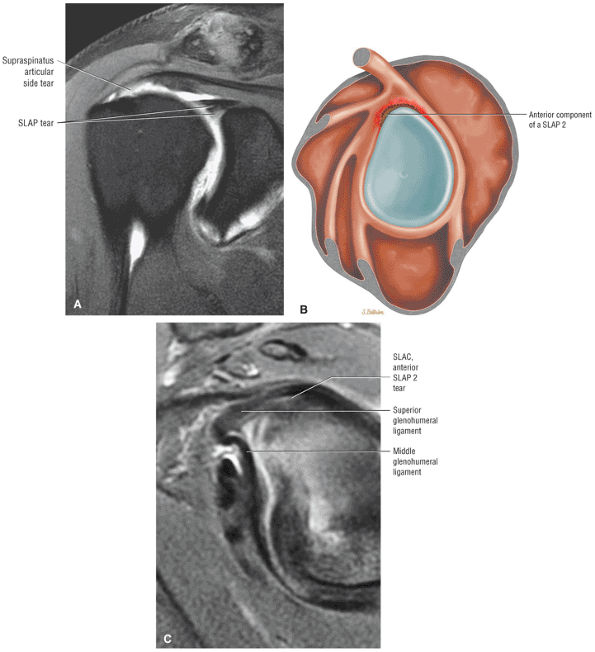

FIGURE 8.1 ● (A) Axial cross-sectional illustration showing a steeper (greater slope) obliquity of the supraspinatus tendon relative to the supraspinatus muscle. Coronal oblique MR images are correctly prescribed using image locations parallel to the supraspinatus tendon. Images improperly obtained parallel to the supraspinatus muscle and not the tendon will foreshorten the supraspinatus tendon in the coronal plane and lead to a potential misdiagnosis of a rotator cuff tear. (B) A T1-weighted coronal oblique MR arthrogram shows the continuity between the supraspinatus muscle and tendon (long white arrow), biceps labral complex (BLC), biceps tendon (b), and coracoacromial ligament (small white arrow).